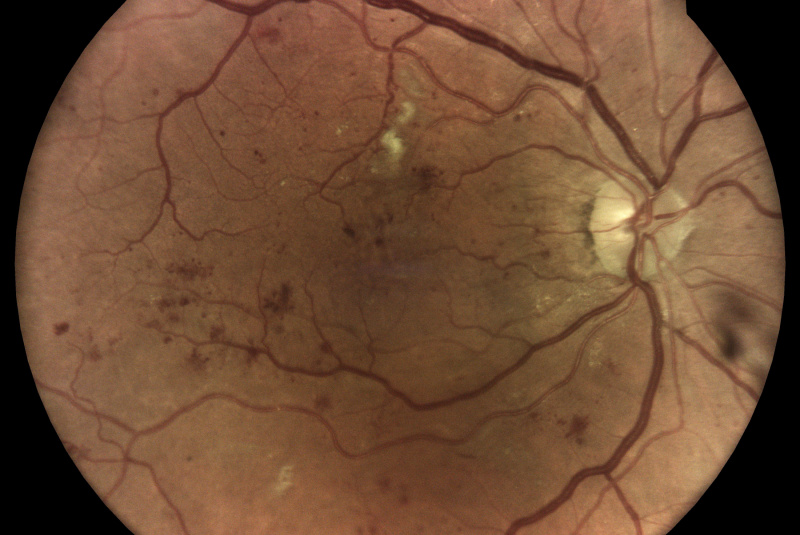

AI (umělá inteligence) okamžitě rozpozná práznaky diabetické retinopatie a klasifikuje výsledky podle závažnosti na základě mezinárodních klasifikací. Získáte přehled s hodnocením závažnosti záchytu, kde po analýze snímků zachycených kamerou iCare DRS Plus je automaticky generován report o pacientovi se stupnicí závažnosti pro diabetickou retinopatii na základě mezinárodních standardů (ICDR, AREDS).

Fundus kamera iCare DRSplus pořídí celkem 4 vysoce kvalitní True Color snímky (dva z pravého a dva z levého oka), které se automaticky ukládají na cloud a posílají se na zpracování AI - umělé inteligenci. Report je dostupný ihned a ten je možno konzultovat s pacientem během téže návštěvy u lékaře.